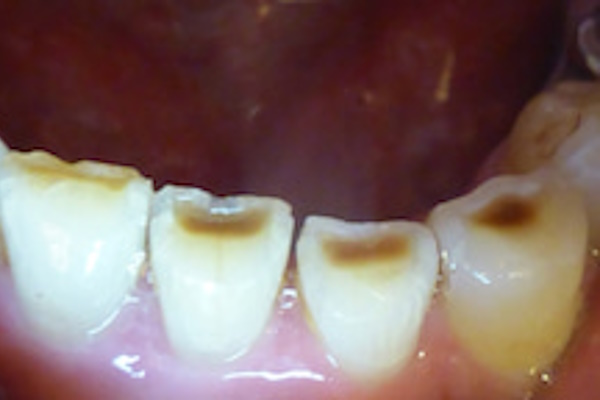

楔状欠損(くさびじょうけっそん)

歯の表面を守るエナメル質が欠損してしまうため、冷たいものがしみるなどの知覚過敏の症状も出てくることが多くあります。

また、歯の生え際の部分に発生するために目に付きやすく、審美的な問題にもつながってしまいます。

くさび状欠損から亀裂に発展し、破折につながるというケースもありますので、なるべく早く原因を追求し、強い咬合力からいかに歯を守るかを考えなければなりません。